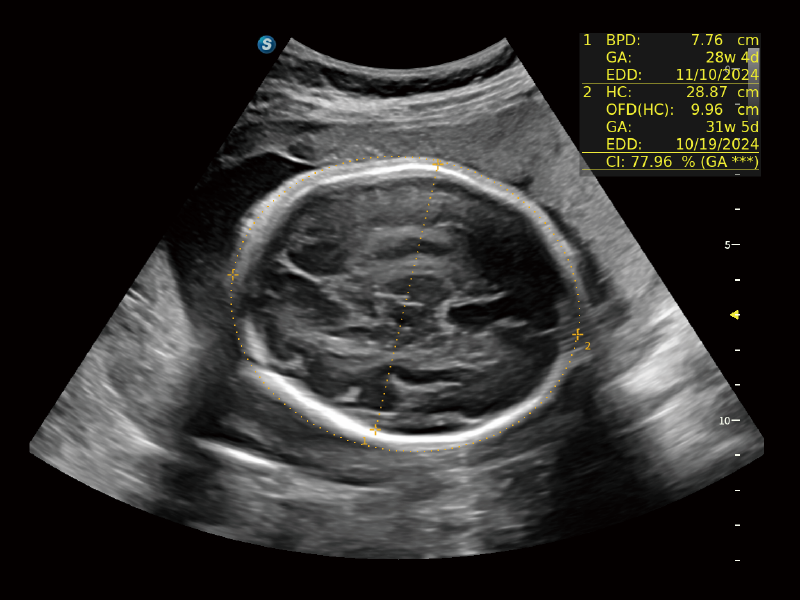

夢(mèng)溪?P80以“關(guān)愛(ài)女性”為基石,提供全方位的解決方案,量身定制以滿(mǎn)足女性的健康需求,涵蓋婦科、生殖健康檢查、產(chǎn)前篩查及產(chǎn)后康復(fù)等領(lǐng)域。

作為開(kāi)立醫(yī)療全新打造的超高端旗艦超聲產(chǎn)品,從探頭抬起喚醒開(kāi)啟掃查到多維探頭發(fā)射接收,通過(guò)先進(jìn)的場(chǎng)成像發(fā)射、自適應(yīng)聚合重建等技術(shù),基于RF Data原始射頻數(shù)據(jù)在圖像生成、高端功能等方面實(shí)現(xiàn)突破,為婦產(chǎn)科、兒科提供全方位臨床解決方案。